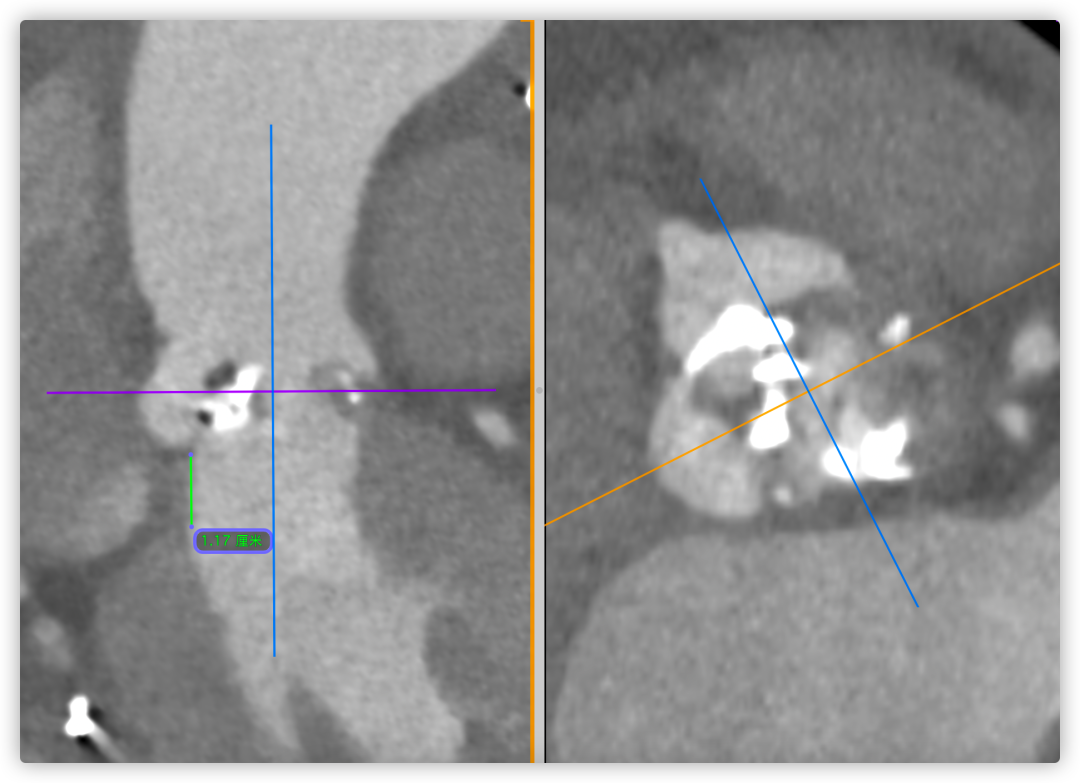

左冠风险评估

间隔膜部